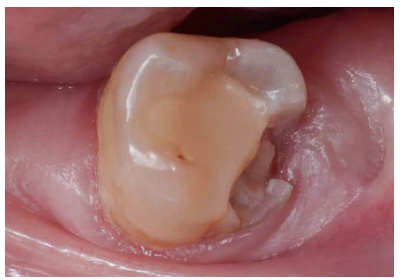

La fluorosis dental es una condición irreversible originada durante el desarrollo dental que genera pigmentaciones intrínsecas, alteraciones en el esmalte manifestadas a manera de manchas blancas, amarillas o marrones, que perjudican la estética y repercuten en el desenvolvimiento social. El presente reporte de caso clínico describe la combinación de los procedimientos de microabrasión y blanqueamiento dental, como alternativas en la eliminación de pigmentaciones dentales. Después del diagnóstico de la patología, verificación de ausencia de lesiones pulpares y caries, una explicación minuciosa a la paciente y obtención del consentimiento informado, se realizó limpieza de las superficies dentales y, bajo aislamiento absoluto, se procedió a realizar la técnica de microabrasión mediante ácido clorhídrico al 6,6% siguiendo las instrucciones del fabricante. Concluido el procedimiento y, observando que era posible mejorar aún más la estética, se decidió ejecutar el procedimiento de blanqueamiento dental, a base de peróxido de hidrógeno al 40% en el consultorio, seguido por peróxido de carbamida al 10% aplicado en el domicilio. Al finalizar el tratamiento se observó uniformidad en el color dental, conjugados con una evidente mejora en la calidad de vida y relación social de la paciente.